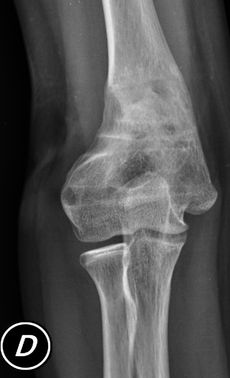

Secuela Fractura Supracondílea de Húmero

Corrección progresiva con tutor hexápodo

Paciente de 12 años. Cuatro años previo a la consulta, presentó una fractura alrededor del codo derecho. A pesar de haberse realizado una cirugía, evolucionó con una deformidad evidente de su extremidad superior. Como alternativa de tratamiento, se propuso una osteotomía a través de una peque inicisión, y corrección progresiva con tutor externo. Esto le permitió mantener la movilidad del codo durante todo el tratamiento. El resultado funcional y estético fue excelente.